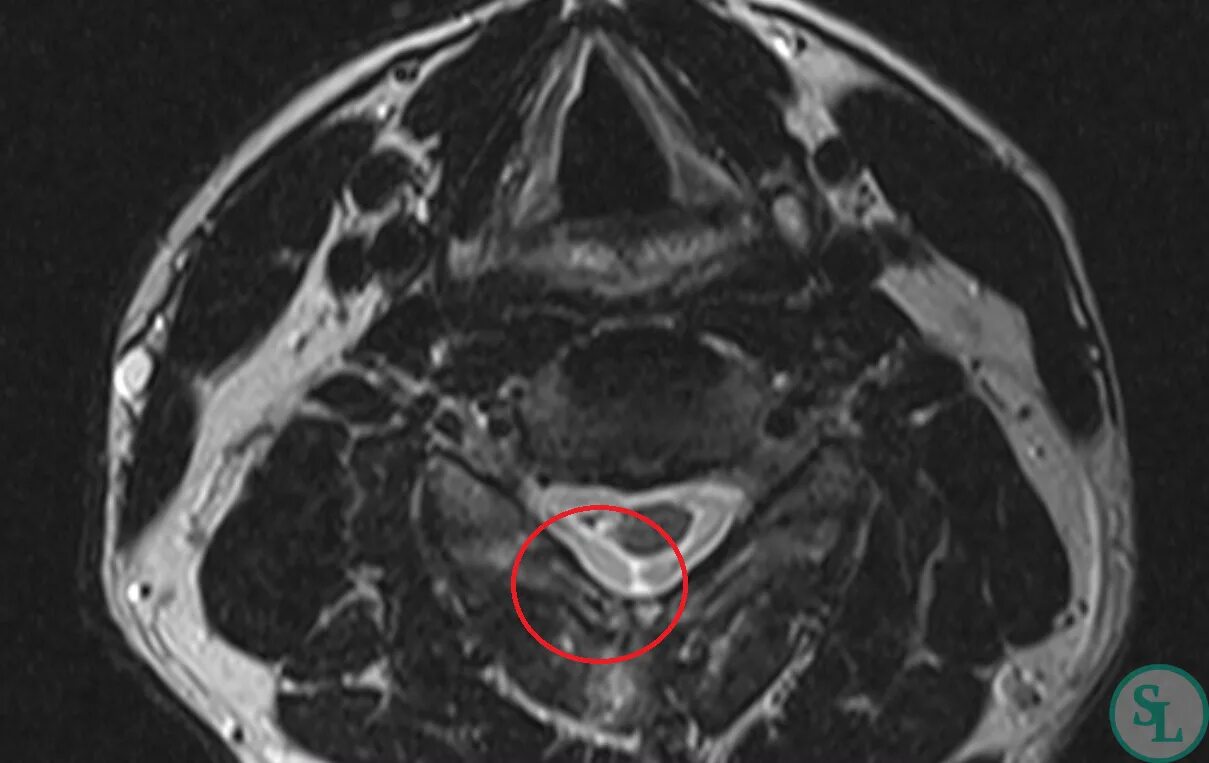

Компрессия дурального мешка что это